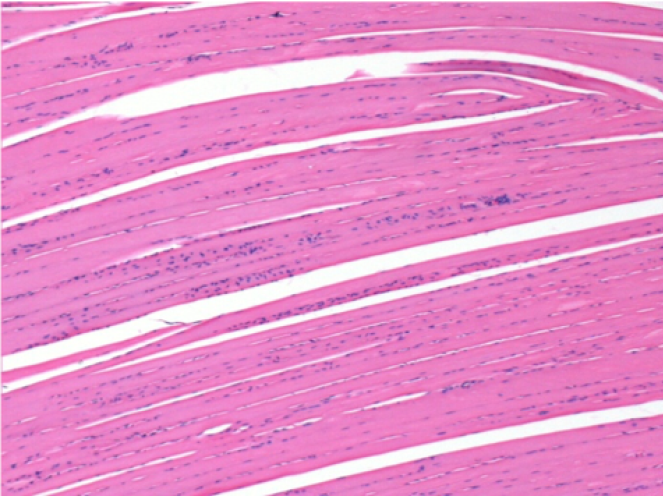

بعد شهر من حقن إندوبيل

بعد شهر واحد من حقن Endopeel 0.1 مل في العضلة أمام الظنبوب اليمنى.

ما يظهر باللون الأسود في الصور ليس نخرًا كما يتصور بعض العلماء!

في الواقع ، يجب أخذ 4 استنتاجات في الاعتبار :

- قطعة أثرية من التلوين

- عدم وجود نخر

- عملية بيولوجية

- موت الخلايا المبرمج

L : Control-100xD30

R:100xD30

R :400xD30